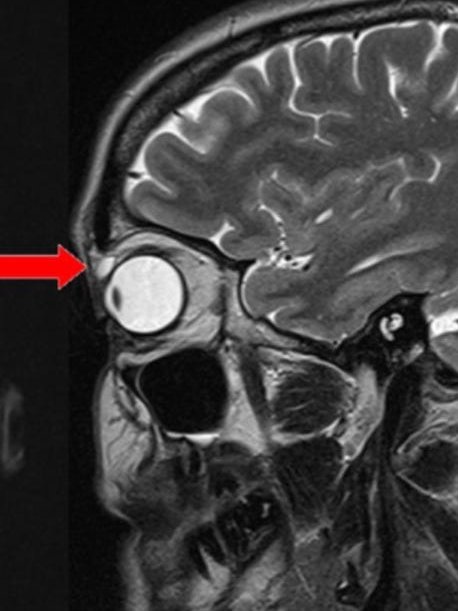

ولكن بعد ستة أشهر، تورم الجفن نفسه، ونمت كتلة عليه وأصبحت مؤلمة عند لمسها. ذهبت كترينا إلى طبيب الأسرة، الذي أحالها إلى طبيب عيون للتحقيق في المشكلة. كانت بصرها جيدًا، وبدا أن كلتا عينيها طبيعيتين باستثناء التورم. لم يكن هناك إفرازات غريبة أو حساسية أو احمرار. ومع ذلك، تمكن الأطباء من الشعور بتكتل صغير تحت جلد الجفن العلوي الأيسر، وقرروا إجراء فحص بالرنين المغناطيسي لمعرفة ماهيته. أظهر الفحص أن الكتلة كانت لها خصائص كيس واضح . كان طوله حوالي ثمانية مللي مترات، وتقع فوق عين المريضة اليسرى مباشرة.

قرر أطباء المريضة إجراء عملية جراحية لإزالتها، وحدث شيء لا يمكن تفسيره في هذه العملية. بعد إزالتها مباشرة، تمزق الكيس وانفتح ليكشف عن عدسة لاصقة هشة للغاية. كانت عدسة لاصقة صلبة، تُعرف أيضًا باسم العدسات اللاصقة الصلبة النفاذة للغاز، لكن المريضة لم تكن ترتدي هذا النوع من العدسات اللاصقة. لم تكن قد استخدمت العدسات اللاصقة الصلبة منذ أن كانت مراهقة